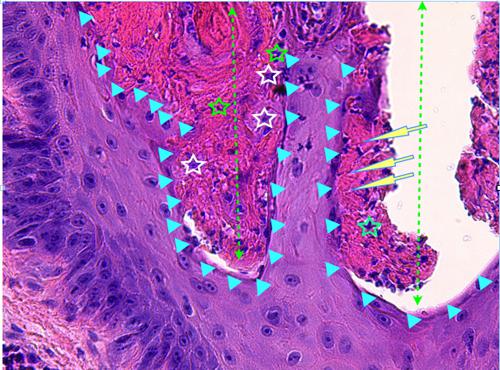

Photo 4 (Hémalun-Eosine X200) peau velue : Vue rapprochée de la Photo 3 montrant

la zone de fissuration de la gaine épithéliale externe d’un infundibula folliculaire avec lyse des

attaches desmosomiales intercellulaires et afflux de granulocytes éosinophiles donnant

naissance à des micro-pustules pariétales multiloculaires.

Légendes de la Photo 4 :

- Double flèche verte : grand axe de l’infundibulum folliculaire

- Double flèche rose : épiderme

- Flèches jaunes : fissuration de la gaine épithéliale externe avec lyse des attaches desmosomiales intercellulaires et afflux de granulocytes éosinophiles

- Ronds marrons : parakératose

- Étoiles rouges : micro-pustules pariétales multiloculaires (folliculite murale) et luminales obstruant l’abouchement folliculaire

- Étoiles turquoises : à gauche infiltrat inflammatoire dermique (au milieu en bas, erreur)

- Étoile vertes : orthokératose